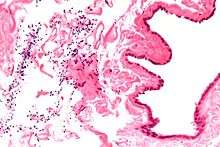

Spermatocele (/spɜːrˈmætəsiːl/[1][2]) is a retention cyst of a tubule of the rete testis or the head of the epididymis distended with barely watery fluid that contains spermatozoa. Spermatoceles are the most common cystic condition encountered within the scrotum. They vary in size from several millimeters to many centimeters. Spermatoceles are generally not painful. However, some men may experience discomfort from larger spermatoceles. They are harmless.

Spermatoceles can originate as diverticulum from the tubules found in the head of the epididymis. Sperm formation gradually causes the diverticulum to increase in size, causing a spermatocele. They are due to continuity between the epididymis and tunica vaginalis.

Finding a painless, cystic mass at the head of the epididymis, that transilluminates and can be clearly differentiated from the testicle, is generally sufficient. If uncertainty exists, ultrasonography of the scrotum can confirm if it is spermatocele.